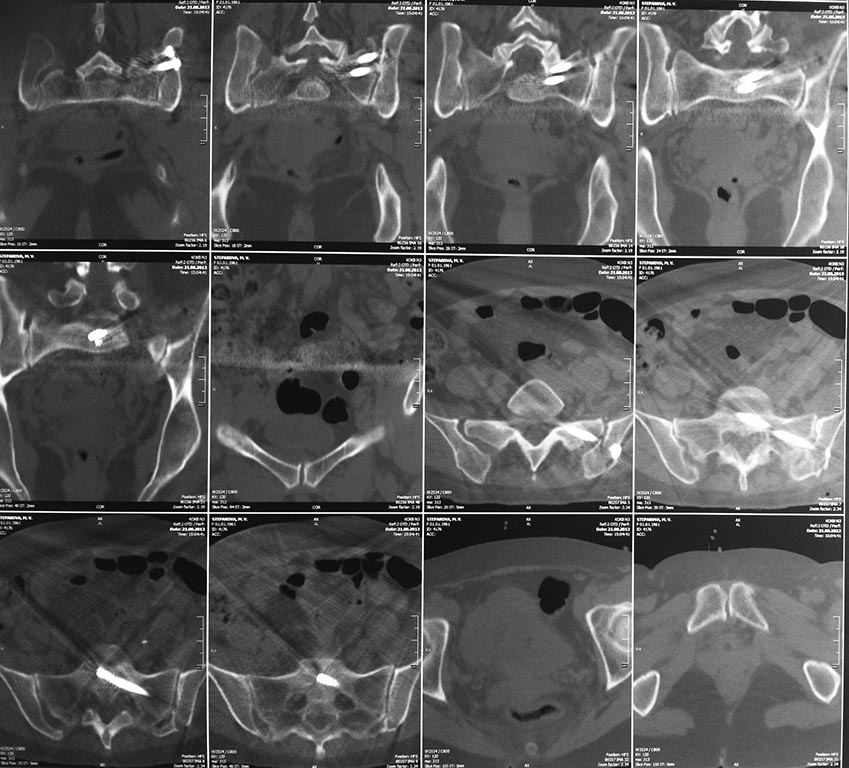

Большое спасибо всем Вам за помощь! Вчера прооперировали пациентку.

Выполнили закрытую репозицию левой половины таза на тракционном столе

под контролем ЭОП, закрытая фиксация левого КПС двумя каннулированными

винтами. Учитывая удовлетворительное стояние отломков лонной и

седалищной костей справа, а так же удовлетворительную ширину лона

передние отделы стабилизировали системой ЦИТО

Винты введены в S1

Послеоперационные КТ прилагаются